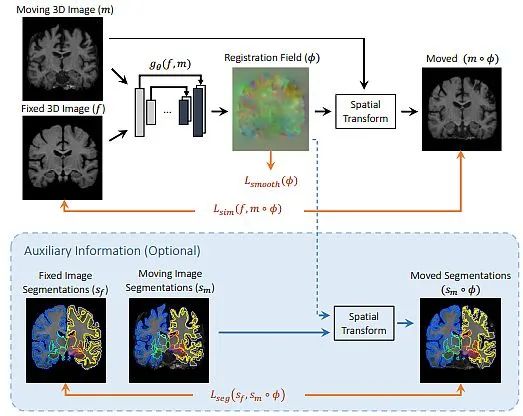

基于深度学习的配准: 它应用卷积神经网络(CNNs)直接从图像对学习变换。它可以处理复杂的变换和大数据集,但需要额外的训练数据。此外,在训练期间计算成本较高。

医学成像

医学图像配准旨在找到最佳的空间变换,以最佳地对齐现有的解剖结构。它被广泛应用于许多临床应用中,例如图像重建、图像引导、运动跟踪、分割、剂量积累等。医学图像配准是一个宽泛的主题,可以从不同的角度来考虑。

从输入图像的角度来看,配准方法可以分为单模态、多模态、跨患者和同患者配准。从变形模型的角度来看,配准方法可以分为刚性、仿射和可变形方法。从感兴趣区域(ROI)的角度来看,配准方法可以根据解剖部位分组,例如大脑、肺部配准等。